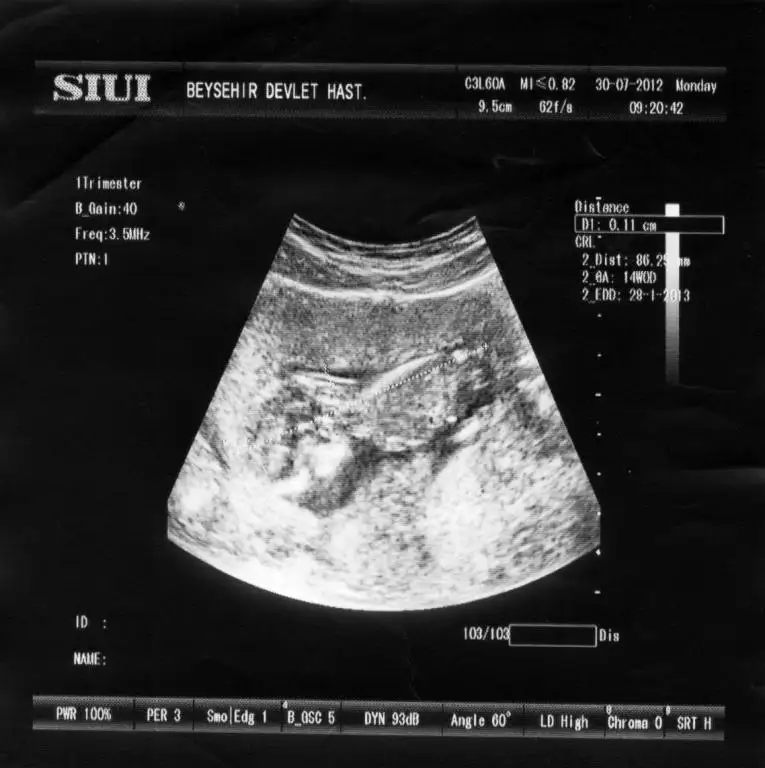

evet bugün benimde dr randevum var bakalım ne resimle geleceğiz .gerçi sata göre 11+2 bugun.ama eimde 3 ayrı haftalarda ki görüntülerim hep sat haftasından 5-6 gün geri.sanırım geç döllenme vs.

evet orada tam 12 haftalık :) ben anlayamadım 3 tane çıkıntı görüyorum orda :) inş dediğin gibi olur. evet bide poz vermiş valla :)